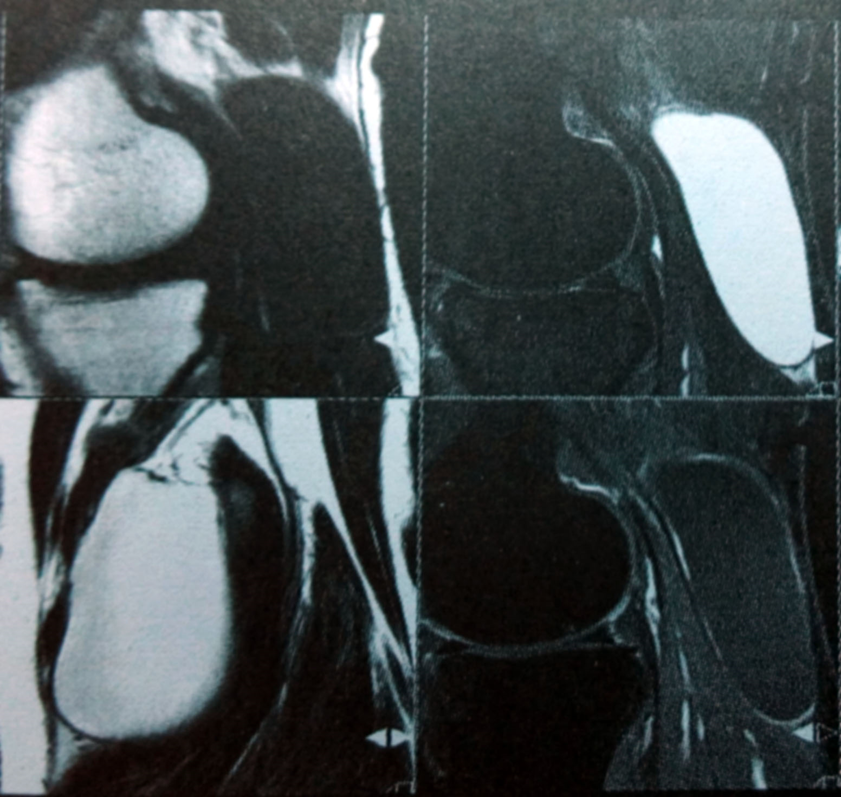

MRI表现

• 外侧半月板囊肿典型MRI表现为半月板撕裂附近的边界清楚的圆形囊肿,并见囊肿有连接部与半月板相连,可形成“吹气球征”(确诊的依据之一)。大部分伴有半月板水平撕裂和关节积液。半月板撕裂在T2WI上可看见半月板内高信号的液体;

• 在 T1WI上呈均匀的低信号,在 T2WI上呈均匀高信号。部分可见线条状低信号分隔;

• 但当半月板囊肿内有血性或凝胶状液体,蛋白含量增多时,在 T1WI 上信号强度可能有所变化,呈中等或高信号;

• 按其发生所在的部位分为半月板内型囊肿、半月板旁型囊肿、滑膜囊肿,以半月板旁型囊肿常见,发生于外侧半月板的囊肿较内侧半月板多。